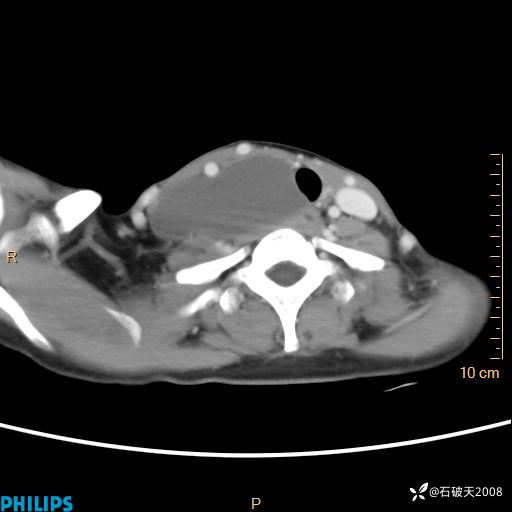

影像诊断要密切结合临床,真的很有必要(病理已公布)

女 21岁 主 诉:发现右侧颈部肿物18年余。

现病史:18年余前患者无明显诱因发现颈部偏右侧有一肿物,具体大小不明确,咳嗽、憋气时肿物增大,局部无疼痛,无吞咽不适,无胸闷及呼吸困难,至当地医院检查考虑良性病变(具体不详)并未做特殊处理,现患者自觉肿物随年龄增长而进一步变大,今日至我院行颈部CT平扫+增强提示:1.右侧颈根部、锁骨上窝及纵隔内异常密度影,考虑良性病变,淋巴管瘤?囊肿?请结合临床。2.双侧颈部小淋巴结。建议结合临床及其他相关检查。现为行进一步治疗,门诊以“颈部局部肿物”为诊断收住我科,发病来患者神志清,精神可,饮食睡眠可,大小便正常,体重无下降。

动脉期